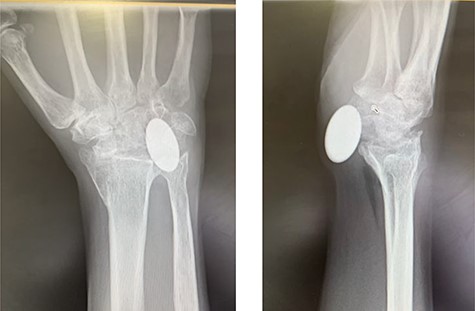

Radiographs demonstrated that the Pyrocarbon implant was palmarly displaced and rotated 90 degrees; it had migrated into the carpal tunnel/ distal forearm (Fig. 2). The clinical diagnosis was compression of the ulnar due to the migration of implant. Surgery was carried out 1 month later during which the Pyrocarbon Amandys wrist implant was removed through a volar approach (Fig. 3) and total wrist fusion was performed using a straight Arbeitsgemeinschaft für Osteosynthesefragen (AO) wrist fusion plate (Fig. 4). The surgery successfully relieved all wrist pain and was accompanied by prompt resolution of symptoms of ulnar nerve compression; she was discharged from follow-up approximately 3 months after surgery.

Post-operative radiographs following removal of pyrocarbon implant and total wrist fusion.